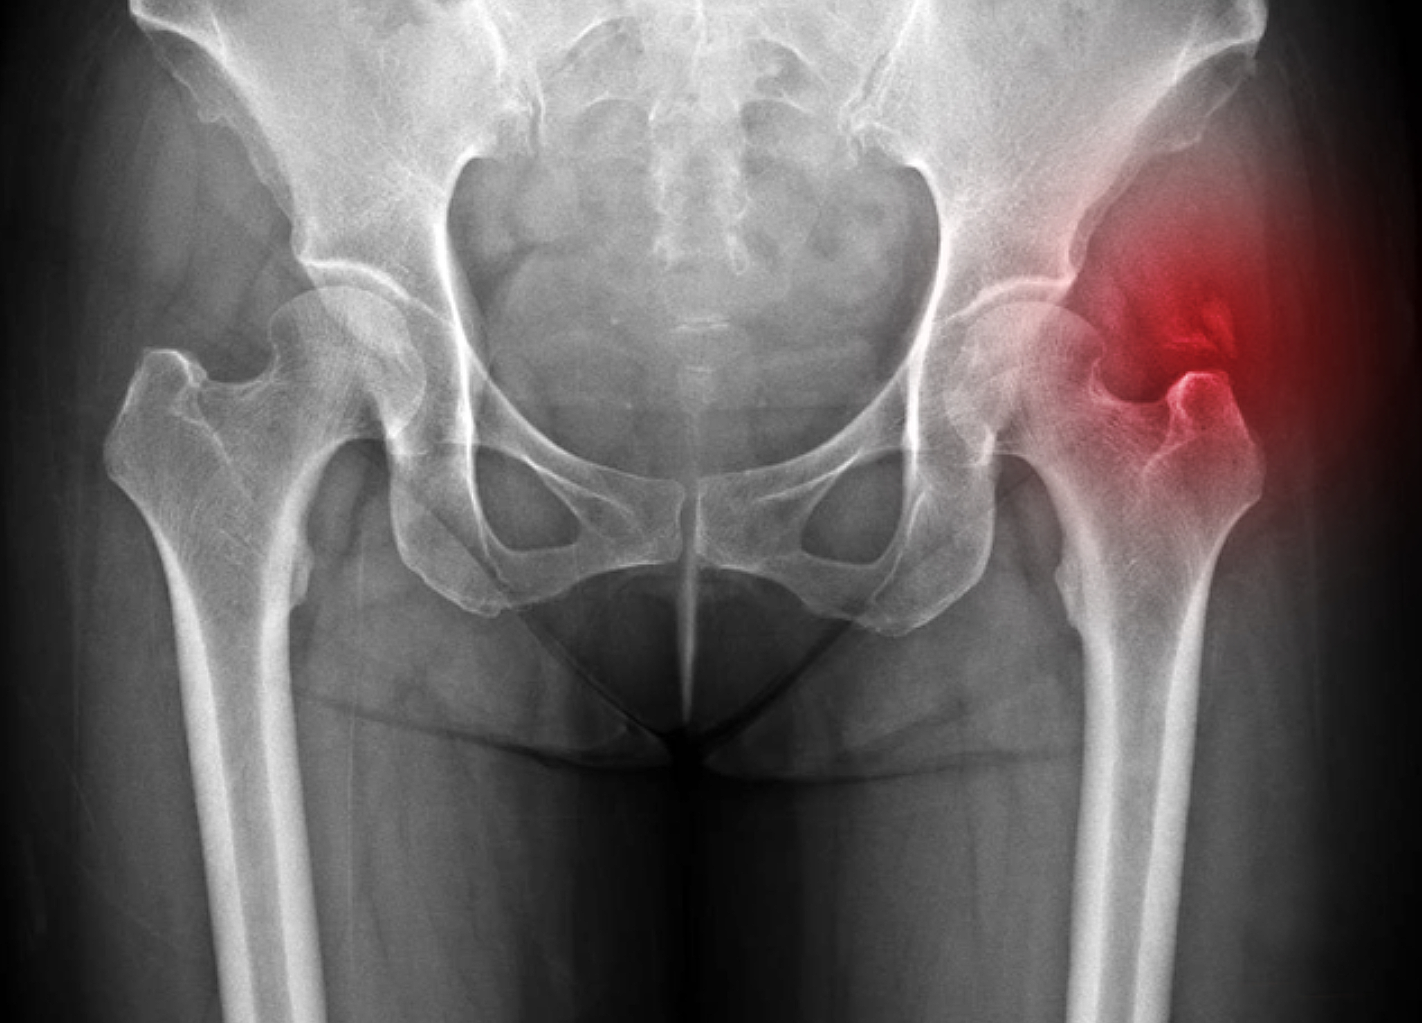

고관절 통증 증상(엉덩관절)은 오른쪽과 왼쪽의 골반과 넙다리뼈가 연결된 관절의 통증을 얘기합니다.고관절은 상체의 하중을 분산시키는 역할을 하며, 걷는 동안 체중의 3배, 달리는 경우 10배에 가까운 하중을 받습니다. 다른 관절과 마찬가지로 감당하기 어려운 충격이나 무게가 가해지면 고관절 통증 증상이 발생합니다. 퇴행성 고관절염, 대퇴골 골절, 대퇴골두 무혈성 괴사, 선천성 고관절 탈구 등이 대표적인 고관절 통증 질환입니다.

고관절은 골반 뼈 속에 공처럼 생긴 대퇴골의 골두가 맞물린 관절입니다. 대퇴골두는 다른 부위에 비해 혈액 순환 장애가 쉽게 올 수 있으며, 혈액 순환 장애는 대퇴골두 무혈성 괴사를 유발합니다. 뼈가 썩으면 몸의 하중을 정상적으로 견디지 못해 미세구조에 골절이 생기고, 심각한 통증이 발생합니다.